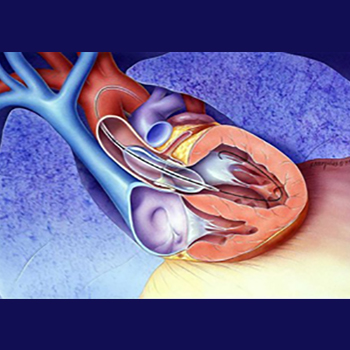

Mitraclip Procedure

Learn more